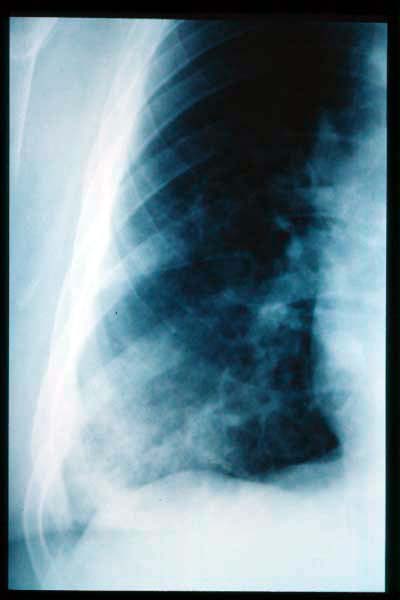

TBC pulmonar antigua